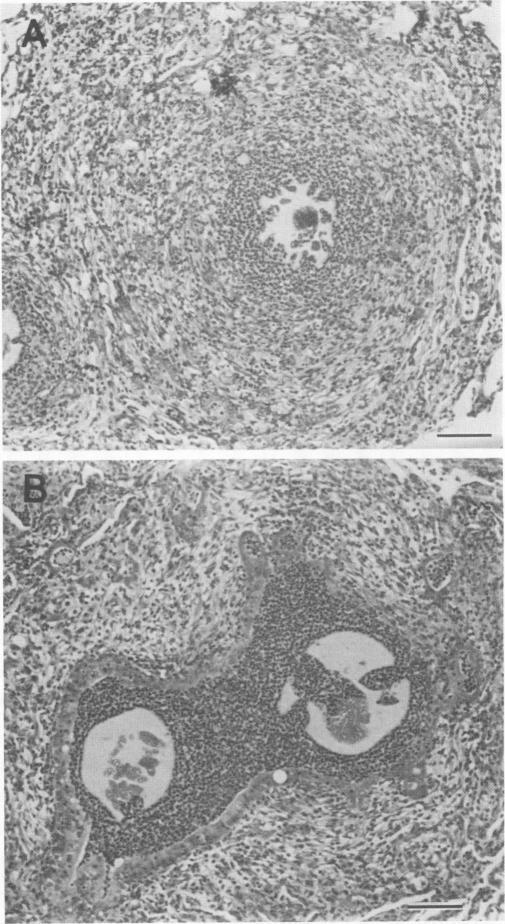

Outer membrane protein F (porin) was purified by extraction from polyacrylamide gels of cell envelope proteins of the Pseudomonas aeruginosa PAO1 strain. Rats were immunized intramuscularly with 25 micrograms of protein F on days 1 and 14 and then challenged on day 28 via intratracheal inoculation of bacterium-containing agar beads. On day 35 the lungs were either fixed for histological examination or submitted for quantitation of the bacteria present. protein F immunization afforded significant protection against challenge with six of six heterologous lipopolysaccharide immunotype strains of P. aeruginosa. By an enzyme-linked immunosorbent assay, the protein F-immunized rats had both immunoglobulin G and M antibody responses to cell envelopes of all six of the heterologous immunotype strains. Protein F immunization greatly enhanced the ability of the rats to clear the inoculated P. aeruginosa from the lungs and significantly reduced the incidence and severity of pulmonary lesions as compared with those in bovine serum albumin-immunized control rats. These data show the efficacy of outer membrane protein F as a protective vaccine in a rat model of chronic pulmonary infection.

外膜蛋白F(孔蛋白)通过从铜绿假单胞菌PAO1菌株的细胞包膜蛋白聚丙烯酰胺凝胶中提取而纯化。在第1天和第14天,用25微克蛋白F对大鼠进行肌肉注射免疫,然后在第28天通过气管内接种含细菌的琼脂珠进行攻毒。在第35天,将肺固定用于组织学检查或送去定量其中存在的细菌。蛋白F免疫为抵御六种异源脂多糖免疫型铜绿假单胞菌菌株的攻毒提供了显著保护。通过酶联免疫吸附测定法,经蛋白F免疫的大鼠对所有六种异源免疫型菌株的细胞包膜都有免疫球蛋白G和M抗体反应。与牛血清白蛋白免疫的对照大鼠相比,蛋白F免疫大大增强了大鼠从肺部清除接种的铜绿假单胞菌的能力,并显著降低了肺部病变的发生率和严重程度。这些数据表明外膜蛋白F作为慢性肺部感染大鼠模型中的一种保护性疫苗具有有效性。